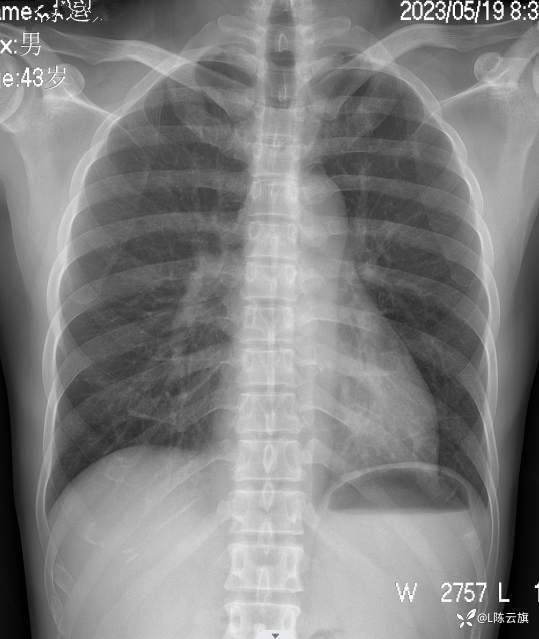

胸片3: